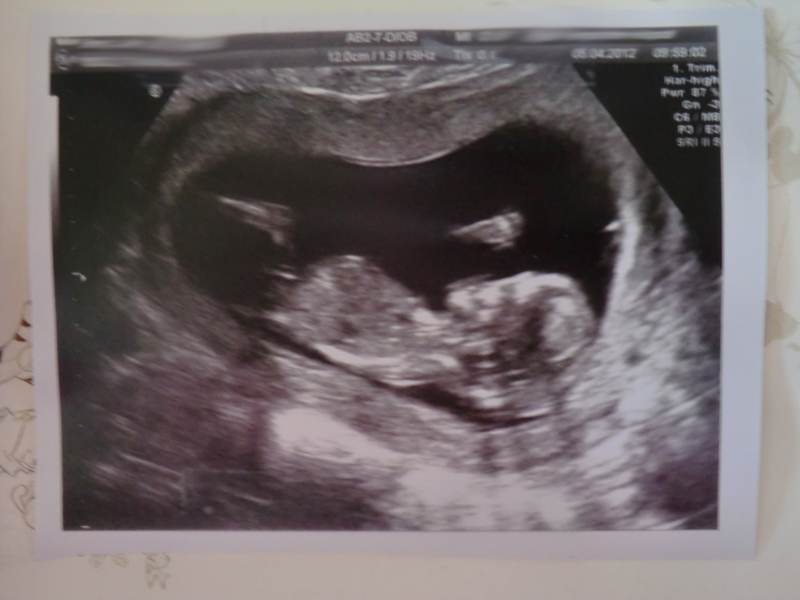

My 12+6 scan pics!

Does the top one look boyish?

Baby had his/her legs crossed the entire time, and kept bringing it up to their chest... also the angle wasn't quite right so it was hard to see a nub and I can't be definite I saw one at all during the scan (saw it so easily with DS) although it looks like there might be a nub in these pictures.

If that's the nub I'm seeing, it definitely looks girly to me!!! :cheer:

First pic makes me think boy, second pic makes me think girl.

however the skull looks very girly to me and I still have a gut feeling you have a girl growing in there so I will stick with

If that's the nub we are seeing, I'm guessing: :DD:

The last pic looks girly to me.